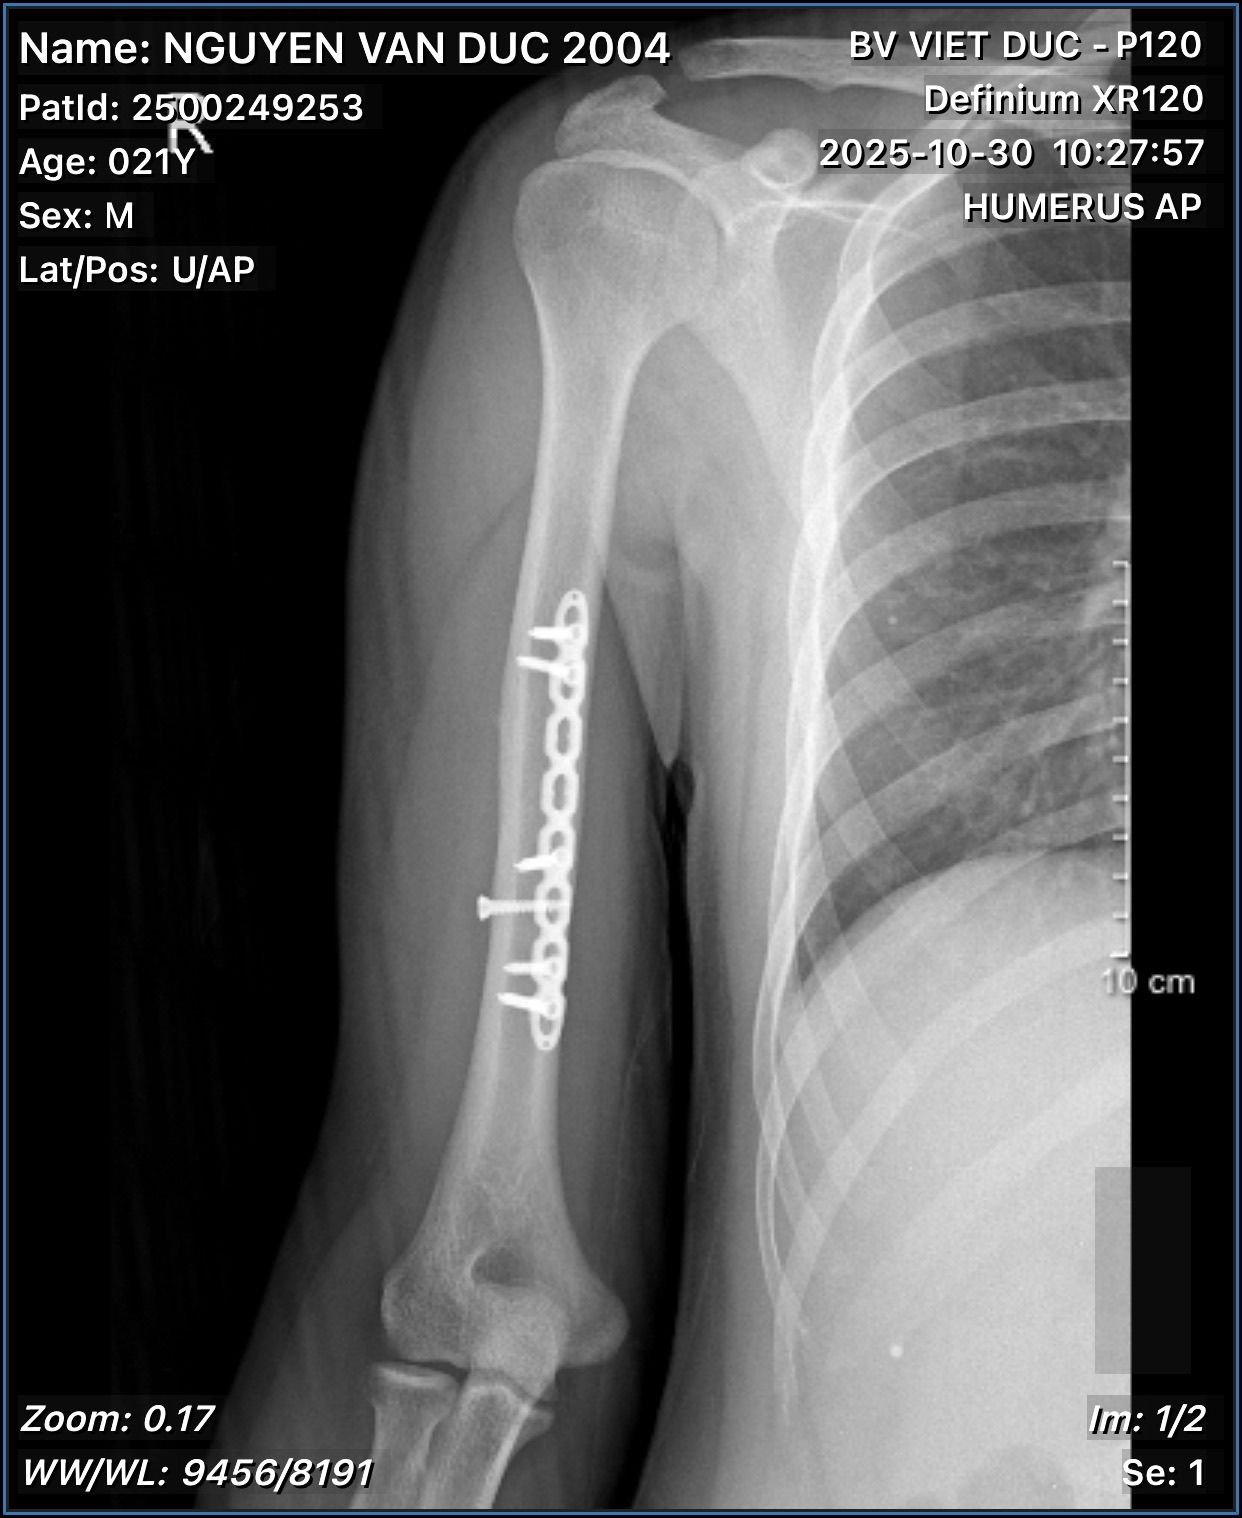

Bác sĩ ơi cho em hỏi đây là ảnh phim sau 1 năm gãy xương cánh tay của em, qua ảnh thì xương của em đã liền được tốt chưa ạ và có thể chơi thể thao chưa ạ

Hình ảnh liền xương tốt rồi em. Tuy nhiên chưa nên chơi thể thao sớm. Em có thể tham khảo ý kiến bác sĩ phẫu thuật